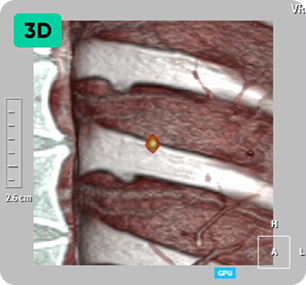

자동 결절 감지

및 폐 RADS 계산

영상 인공지능을 활용해 저선량 흉부 CT에서 놓치기 쉬운 폐 결절을 탐지하고 분석합니다.

환자의 상태를 파악하여 효율적으로 진단합니다.

미세 결절을 발견하면 기본 정보, 결절 개수, 크기 및 상태, RADS 범주 등 다양한 정보를 얻을 수 있습니다. 폐암으로 발전할 가능성이 있는 소견도 미리 확인하여 작업 시간을 단축하고 사례에 따라 효율적인 판독을 가능하게 합니다. 미세 결절 검출: 결절 개수, 크기, 상태, RADS 범주에 대한 포괄적인 정보 제공 잠재적 폐암 발생을 조기에 발견하여 시간 효율적인 스캔 판독을 가능하게 합니다.

작은 것부터 큰 것까지 다양한 크기의 결절 감지